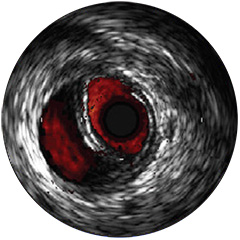

Digital IVUS imaging

imaging

imaging

imaging

Orientación IVUS

es "definitivamente beneficiosa" para los pacientes, y dio lugar a un cambio de los planes de tratamiento el 74% de las veces 1,6,7

Figura 1

Figura 2